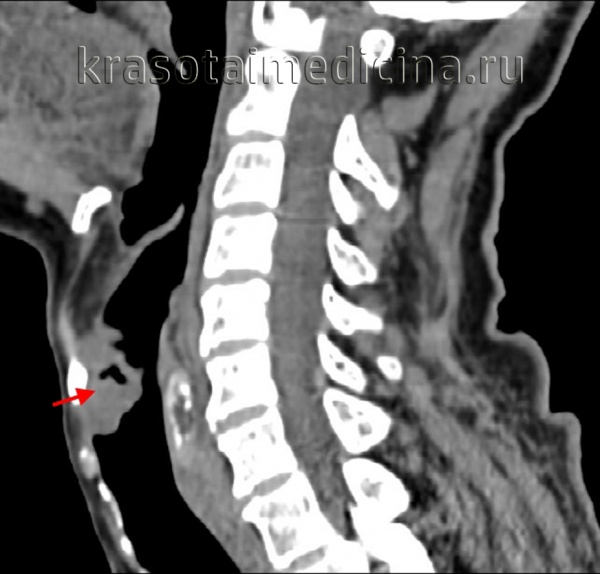

КТ шеи. Рак связок гортани справа.

Дополнительными методами диагностики рака гортани являются исследования голосовой функции, которые позволяют оценить подвижность голосовых связок, форму голосовой щели К ним относятся стробоскопия, электроглотография, фонография. Распространенность рака гортани оценивают с помощью рентгенографии и МСКТ гортани. Наличие метастазов в тканях шеи выявляется ультразвуком. Для определения регионарных метастазов проводится биопсия лимфатических узлов.